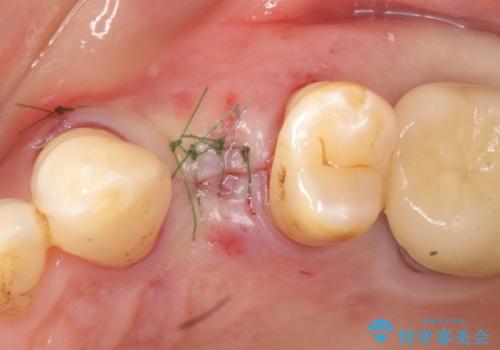

精査したところ、歯が割れており保存不可能な状態であったためやむなく抜歯しました。

患者様のご希望によりインプラント治療を行いました。

- ¥350,000 (インプラント、minor GBR、土台、仮歯、被せ物)費用は治療当時の料金となります

インプラントの種類:スプライン ツイスト

被せ物の種類:メタルボンドクラウン

固定様式:スクリュー固定